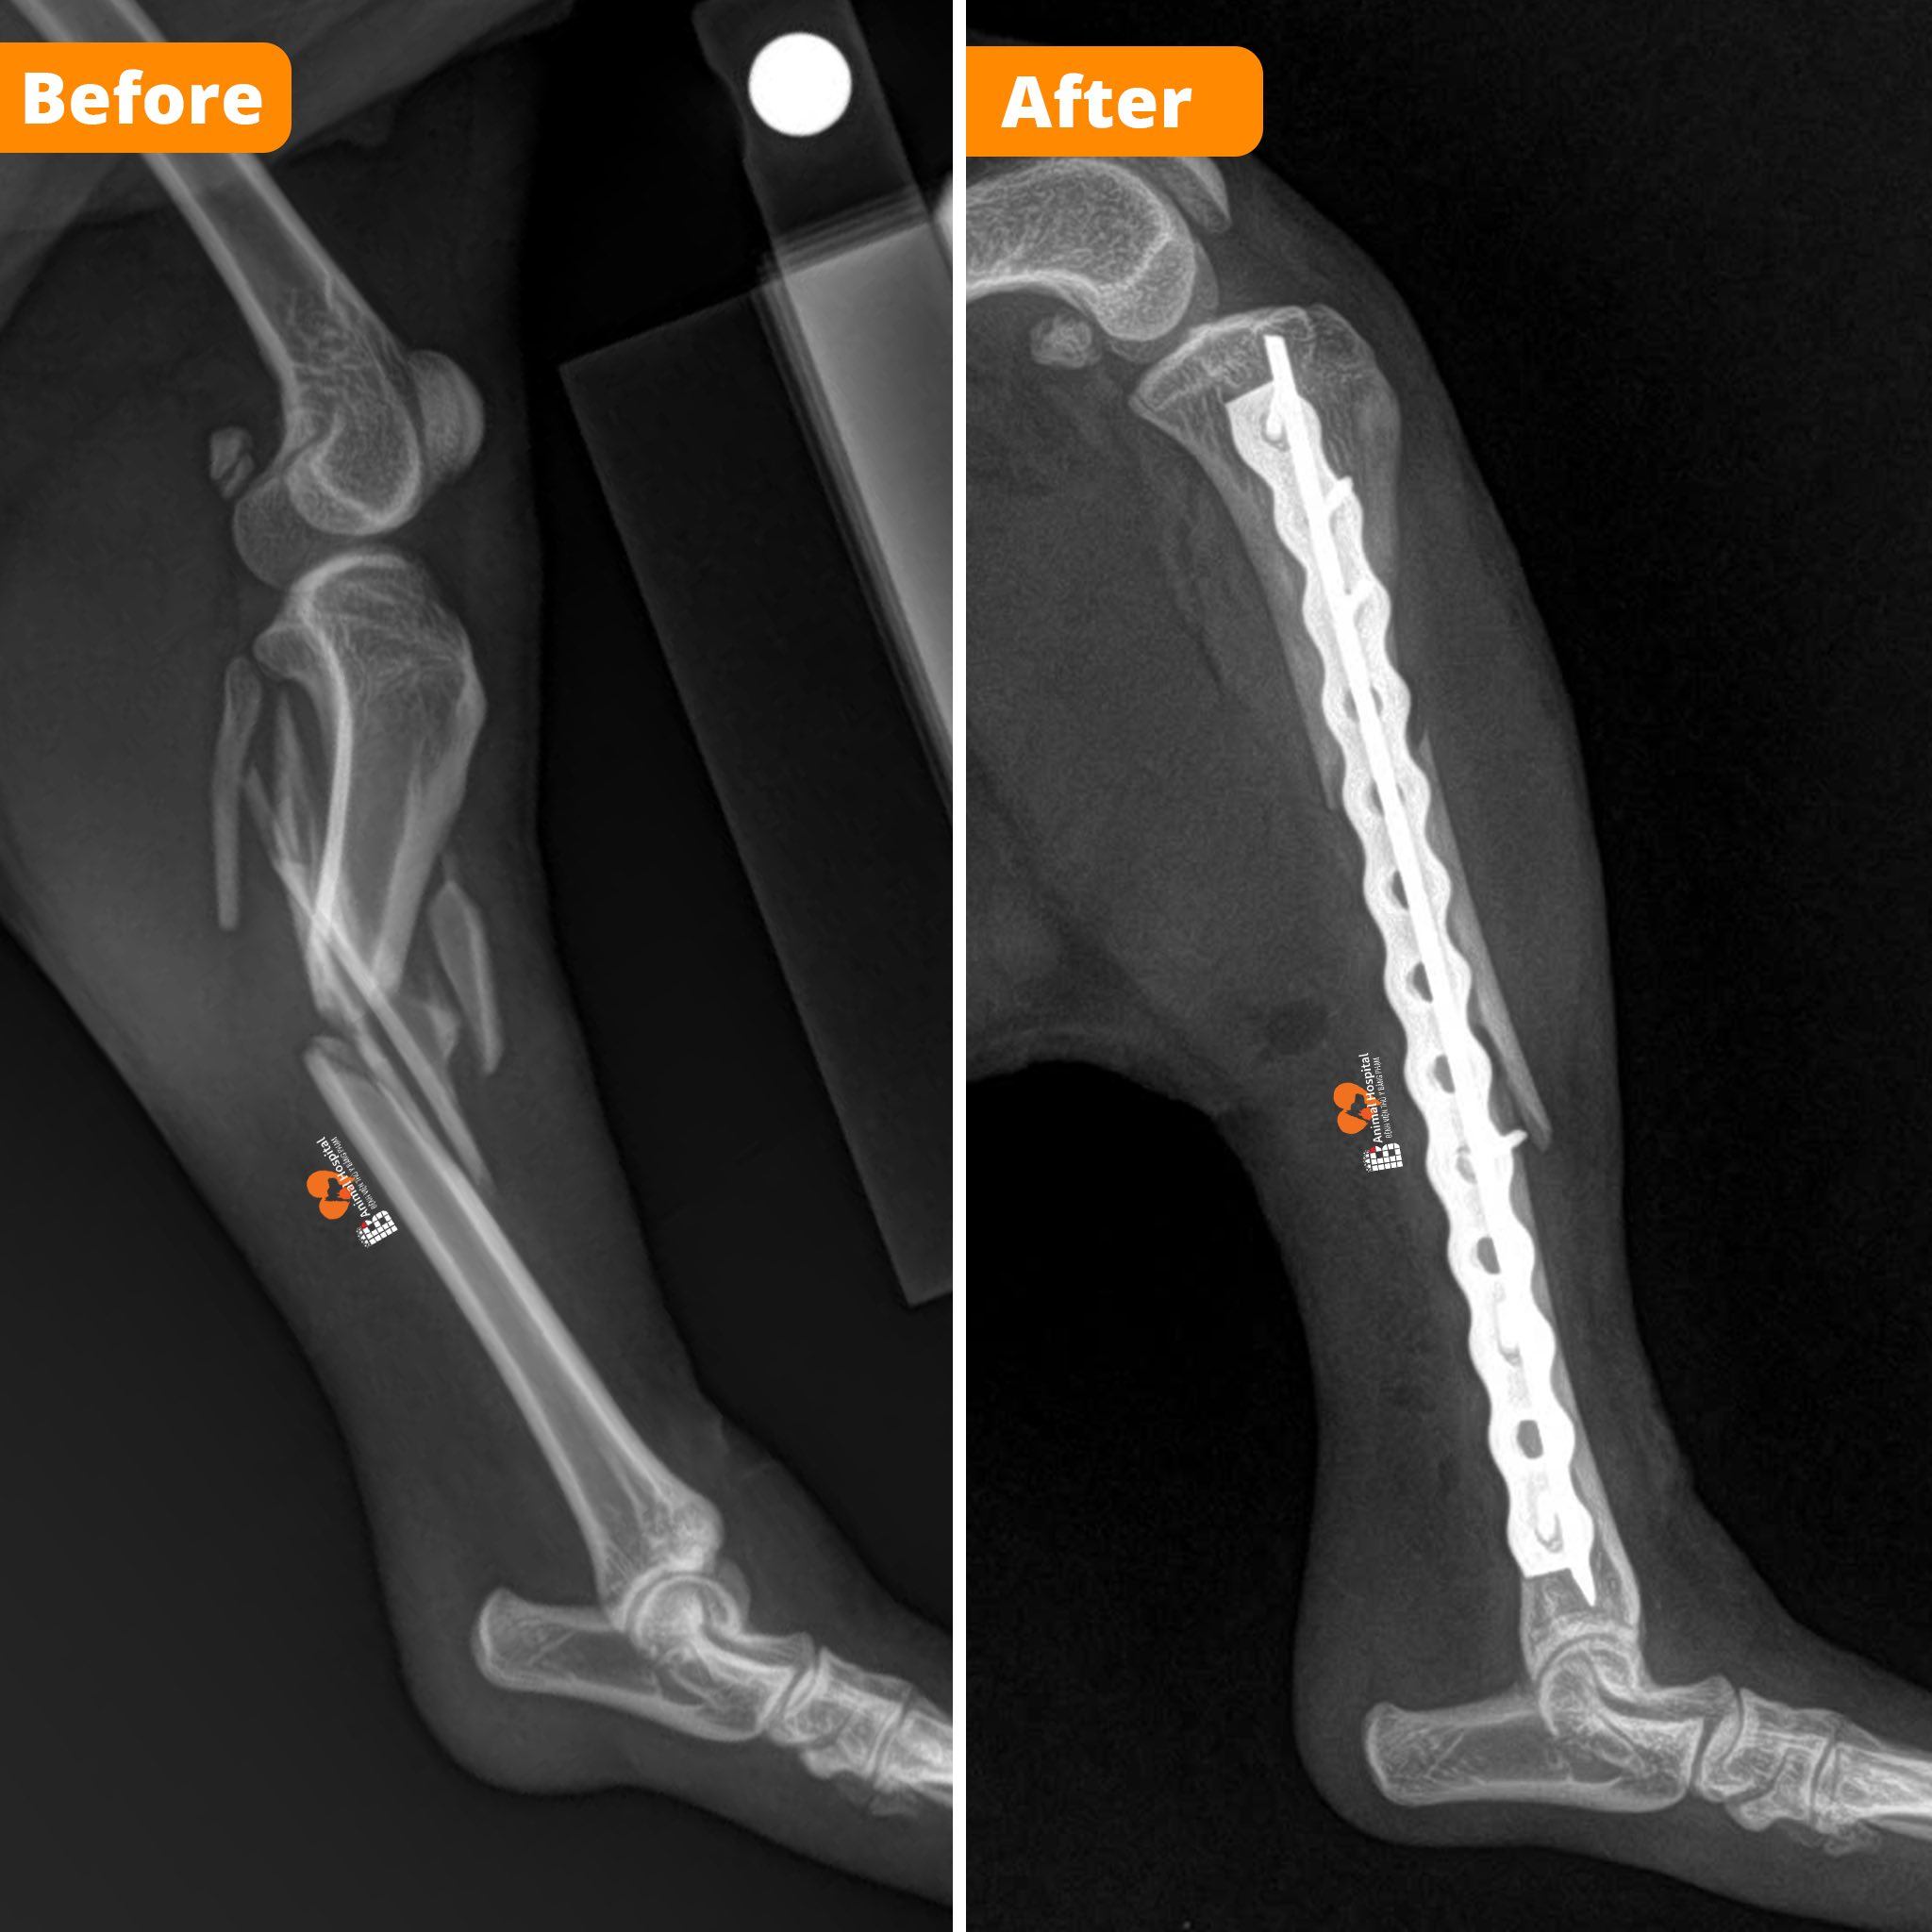

DỊCH VỤ PHẪU THUẬT TPLO – ĐIỀU TRỊ ĐỨT DÂY CHẰNG CHÉO CHO CHÓ MÈO

Phẫu thuật TPLO (Tibial Plateau Leveling Osteotomy) là kỹ thuật chỉnh hình tiên tiến hàng đầu trong điều trị đứt dây chằng chéo trước (CCL) ở chó, giúp ổn định khớp gối và phục hồi khả năng vận động tự nhiên cho thú cưng.

Tại Bệnh viện Thú y Bằng Phạm, các ca phẫu thuật TPLO được lên kế hoạch chính xác bằng phần mềm iBlueVet của BlueSAO – cho phép bác sĩ mô phỏng phẫu thuật trên hình ảnh X-quang trước khi mổ, xác định các thông số tối ưu như TPA, góc xoay, kích thước lưỡi cắt và loại nẹp cố định.

Trong mổ, ekip phẫu thuật sử dụng bộ dụng cụ TPLO của BlueSAO – công nghệ ren kim loại truyền thống có độ bền vượt trội, ổn định lâm sàng cao và tuổi thọ dài, đảm bảo kết quả điều trị bền vững.

Trực tiếp phụ trách kỹ thuật là Giám đốc Phạm Bằng, được đào tạo và chứng nhận quốc tế trong lĩnh vực phẫu thuật chỉnh hình thú y của BlueSAO, chuyên sâu về TPLO, TTA, và các kỹ thuật phục hồi chức năng khớp nâng cao.

Mỗi ca mổ đều được thực hiện trong phòng phẫu thuật tiêu chuẩn quốc tế, có C-Arm hỗ trợ theo dõi tiến trình phẫu thuật theo thời gian thực, giúp kiểm soát chính xác vị trí cắt xương và đặt nẹp.📞 Liên hệ khám & tư vấn